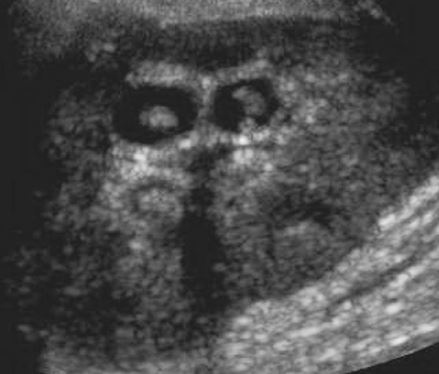

Tubular Ectasia of the Rete Testes

• The rete testes are a complex collection of small tubules that are located in the mediastinum of the testis. Fluid from the seminiferous tubules drains into the rete testis and then exits the rete testis via the efferent ductules. The efferent ductules then converge into the head of the

epididymis.

• Tubular ectasia of the rete testes is believed to be caused by some degree of outflow obstruction of the seminiferous fluid. Perhaps this is the reason why it is frequently associated with testicular cysts and spermatoceles of the epididymal head. It is also more commonly seen in patients with a history of inguinal surgery, such as hernia repairs and vasectomies.

• The key to making the diagnosis and distinguishing tubular ectasia of the rete testes from cystic testicular tumors is to note the bilateral involvement when present and to recognize the elongated shape on long-axis views of the testis.